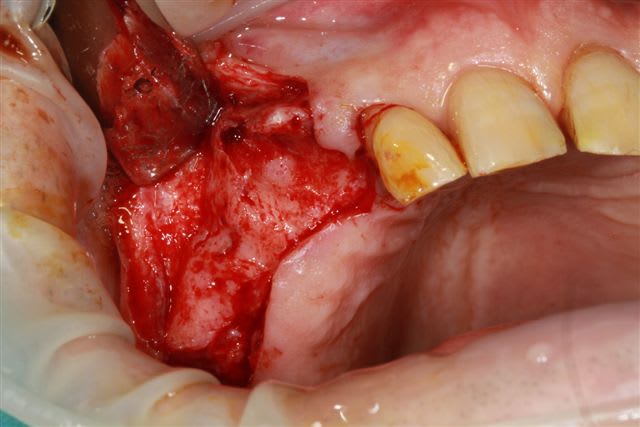

13 fenestration vestibulaire j'utilise la paroi palatine, lame N°15, spreader, expansion et pose d'un 40140